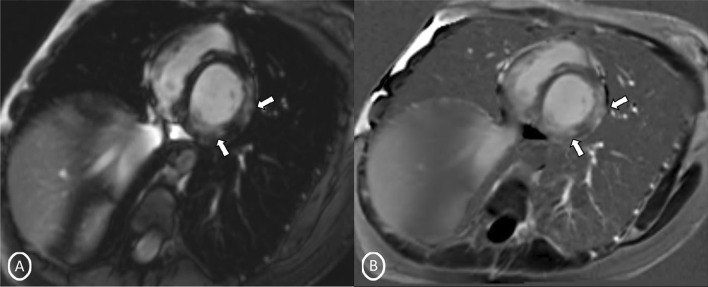

A 19-year-old female had presented to our Emergency Department, complaining of sudden severe chest and epigastric pain since 1 day, which was associated with sweating. The pain was radiating to neck and left arm. The pain did not relieve on rest but subsided on medications. Similar episodes were also reported in the past few days, however, with less severity. The patient confirmed to not having shortness of breath, palpitation, syncope, dizziness, nausea, emesis, fever, or cough. There was no history of any previous cardiac ailment/surgery/other identifiable cardiovascular risk factors or any other history of infection. There is no evidence to suggest chest wall trauma. There is no history of comorbidities or any history of smoking. There is no significant family history or any similar past history. Upon admission, patient was conscious, alert with heart rate of 86 bpm, blood pressure measuring 110/60 mm Hg, 97% oxygen saturation at room air, temperature of 36.4 °C, and respiration rate of 15 breaths/min. The cardiac biomarker troponin T levels were extremely raised, measuring 50,000 pg/ml, and CK-MB was raised, measuring 111U/Lt. Laboratory findings showed that inflammation markers were normal, C-reactive protein (5.8.0 mg/L) and D-dimer (94 ng/mL). Other laboratory findings such as lipid profile, complete blood count, electrolytes, fasting blood glucose, HBA1c, and renal and liver function tests were normal. Cardiac auscultation showed normal S1, S2 without murmurs or pericardial rub and any sign of heart failure. Initial ECG revealed ST segment elevation in the leads I, aVL, V4, V5, and V6 leads, normal sinus rhythm (60 beats per min) without any other abnormalities (Fig. 1), which was resolved by day 3. Arrhythmias were not found during continuous cardiac monitoring. Echocardiogram showcased an ejection fraction of the left ventricle to be 60%, whereas the echocardiographic metrics were not very significant. Patient was then treated as ACS with a salicylate-based nonsteroidal anti-inflammatory drug (NSAID), anticoagulants, and anti-thrombolytics. CMR was done on 3 T MRI machine with acquisition including T2/STIR Dark blood four-chamber long axis; CINE images in short axis, long axis, RVOT, and LVOT; and early dynamic gadolinium enhancement images and delayed gadolinium enhancement in PSIR images. T2/STIR Dark blood sequences showed T2 hyperintensity in the subepicardial region along left lateral wall (Fig. 2A, B). There was associated mild global hypokinesia with mildly reduced ejection fraction/systolic function (Fig. 3A, B). Patchy delayed gadolinium enhancement of intramural, subepicardial as all tans-mural enhancement with non-involvement of the subendocardium (suggesting a non-ischemic pattern) in multiple segments of cardiac basal (Fig. 4A, B), mid cavity (Fig. 5A, B), and apical cavity—with predominant involvement of lateral (Fig. 6A, B) and inferior wall segments in the basal cavity. There were no signs of infarction of myocardium; therefore, the patient was diagnosed with acute myocarditis (based on Lake Louise Criteria for Acute Myocarditis). Further, viral and autoimmune workups results were found to be negative. It included hepatitis (B, C), human immunodeficiency virus, Coxsackie virus, COVID-19, cytomegalovirus, Epstein–Barr virus (EBV), and Parvovirus B-19. On further analysis and detailed relevant history workup, the patient admitted to using cannabis for the past 1 year with last exposure being 3 days before admission. On the basis of detailed clinical history, findings on CMR with other negative viral markers, and possible etiological factors, a final diagnosis of myocarditis presumed secondary to marijuana/cannabis toxin abuse was made. Patient was released from the hospital on the seventh day with advised conservative treatment. The patient was counseled to abstain completely from cannabis or related drugs. Patient was advised to repeat a CMR control, three months later. A 3–4-month restriction on high-intensity activity was also given to the patient following discharge.